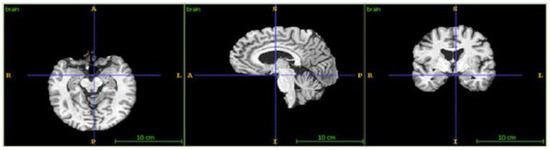

3.2. Image Fusing and Preprocessing

3.3. 3D-Convolutional Neural Network